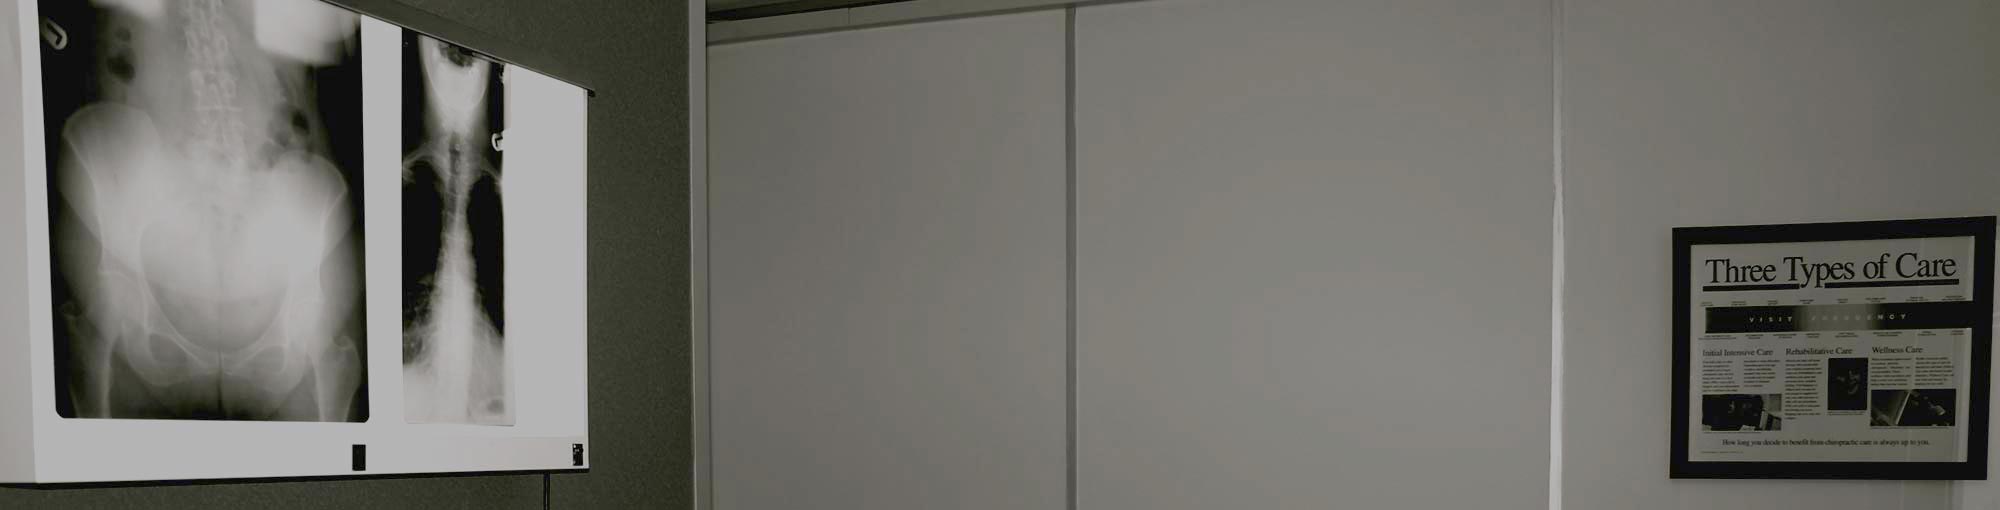

Postural changes through spinal bone misalignment can put pressure on the nerves and brain affecting the billions of signals travelling between the mind and body and effectively blocking and slowing down communications. A Chiropractor removes these spinal misalignments to unclog blockages and improve signalling throughout the body. This is done scientifically,